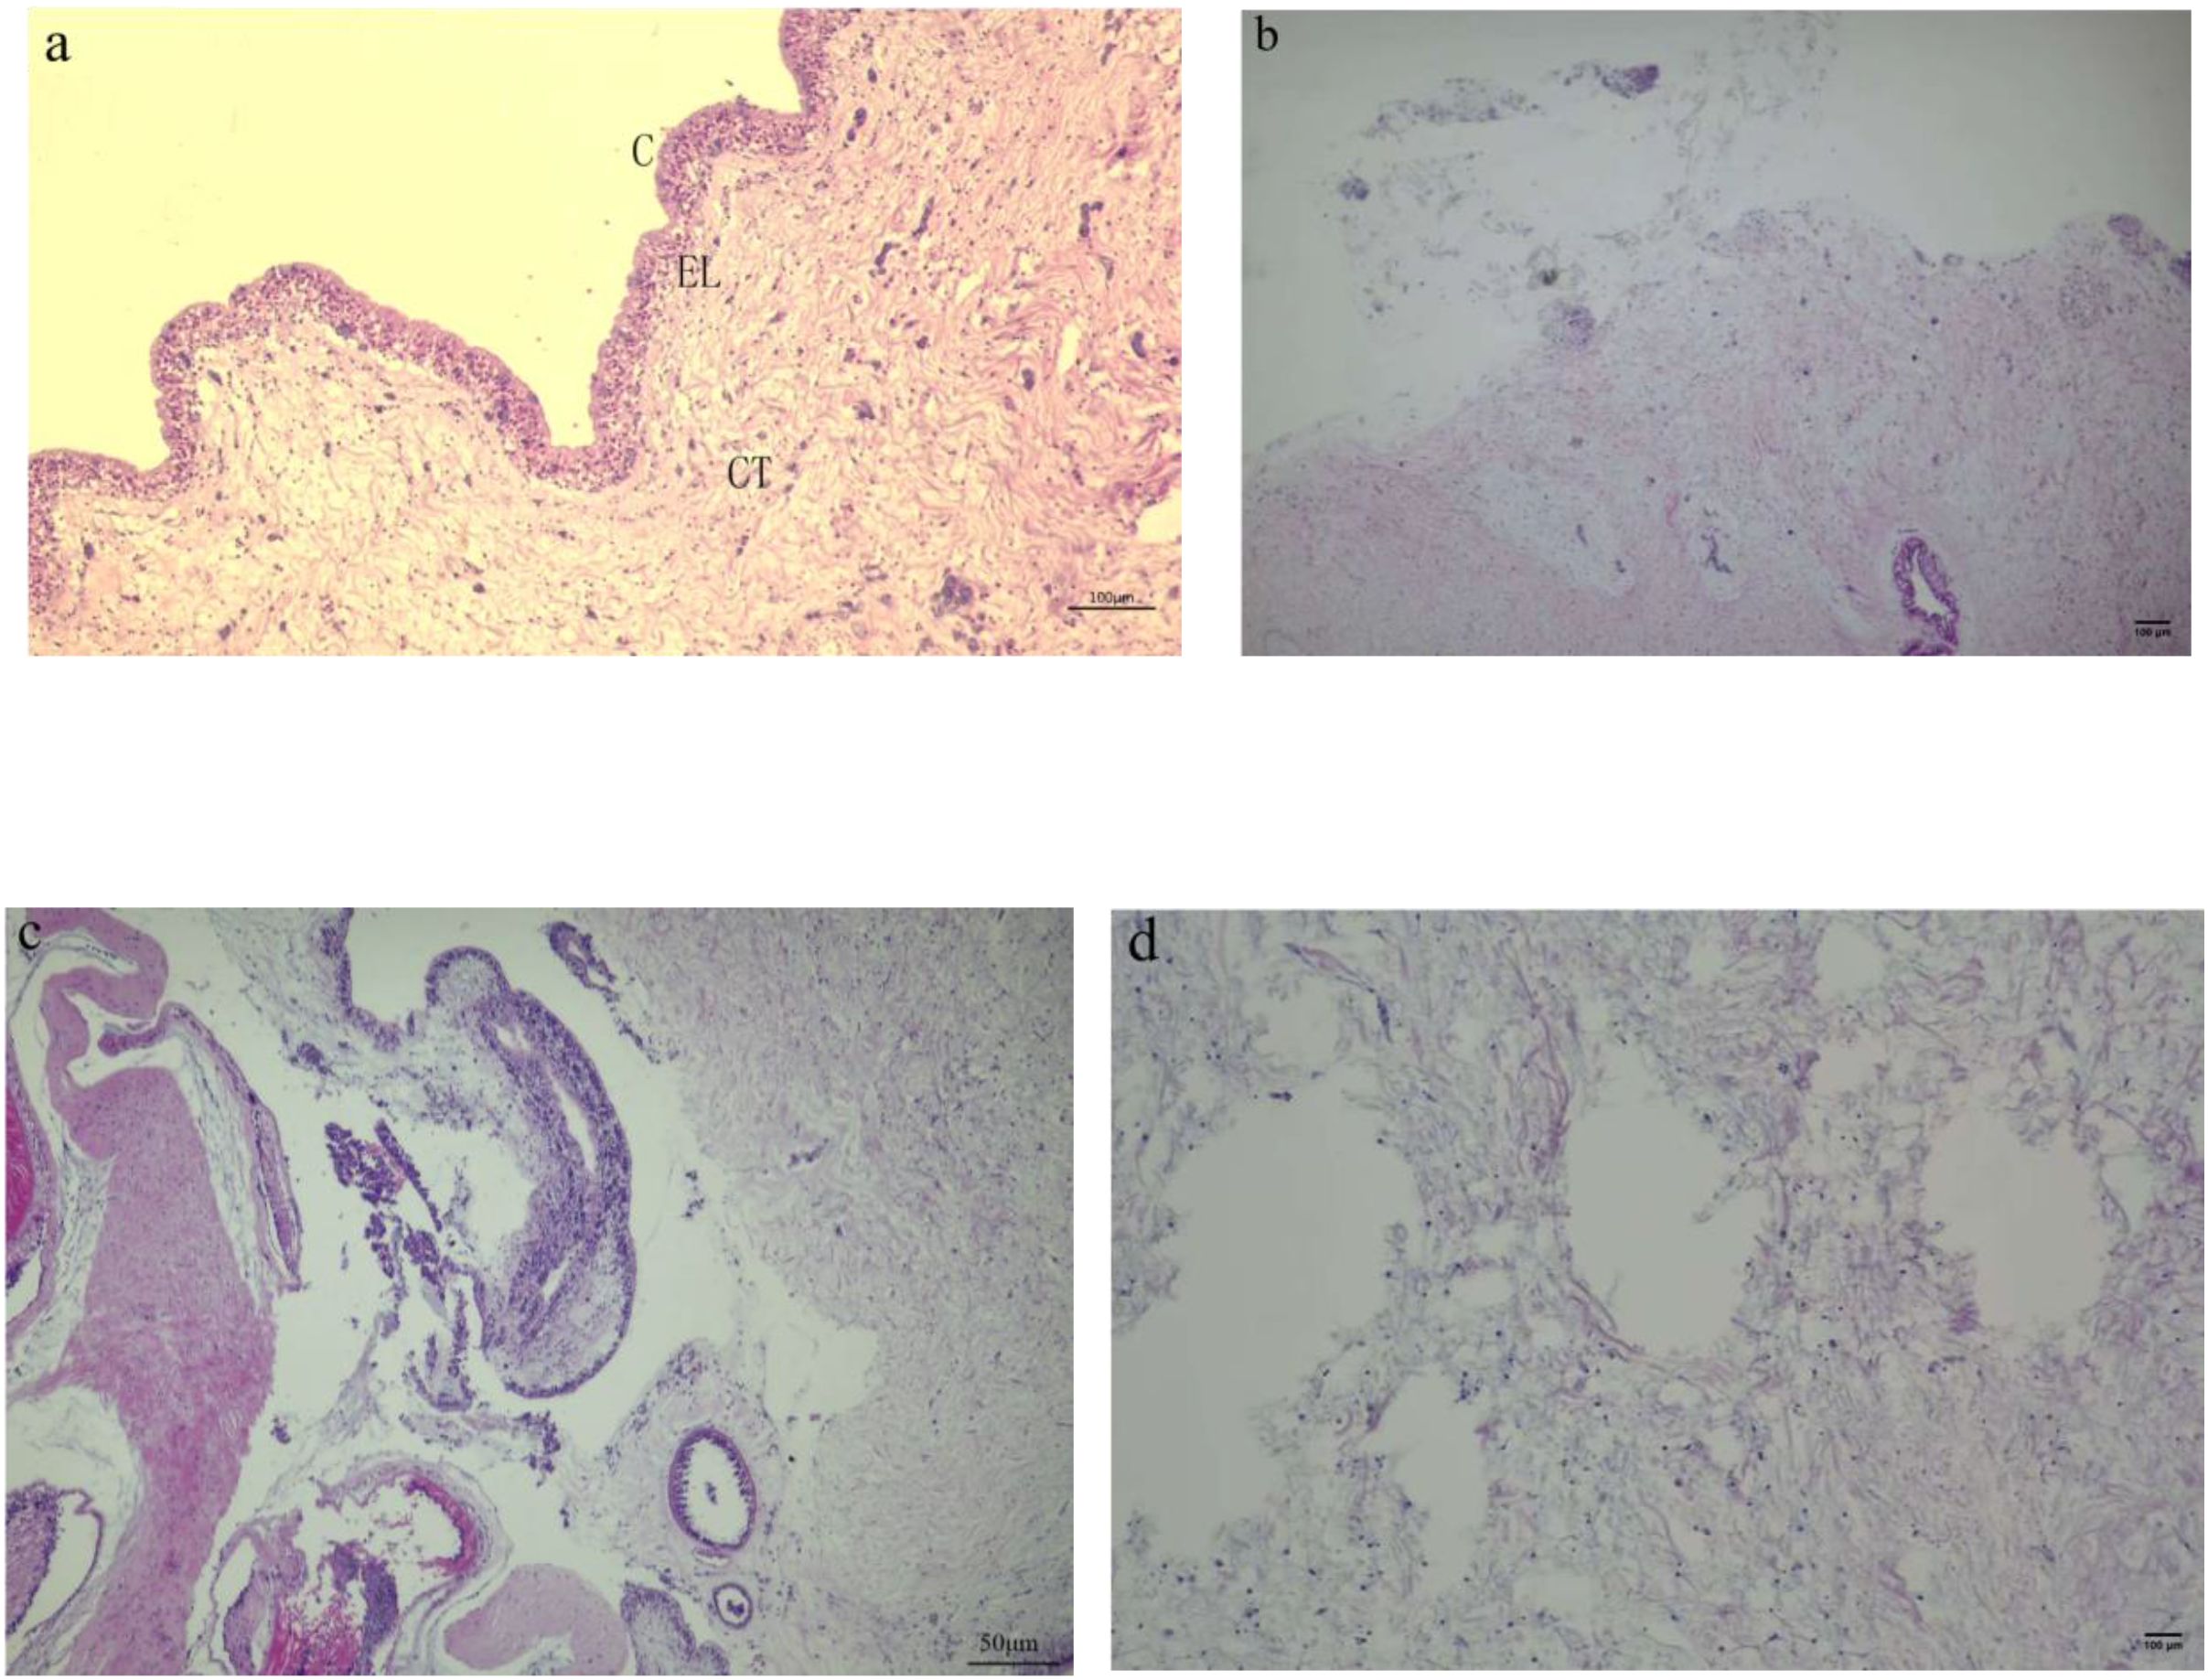

Clinical observations of diseased sea cucumbers revealed the presence of small white erosions around their bodies. The body wall of affected individuals exhibited excessive secretion of white mucus, and most exhibited an inability to move in response to mechanical stimuli (Figure 1). Histopathological examination showed that the epidermis was completely lost over a length of 500 μm in affected areas. Collagen bundles originating from the dense connective tissue extended into the underlying loose connective tissue beneath the area of epidermal loss. The upper portion of the “T”-shaped collagen structure formed by these bundles acts to seal the epidermal defect. Additionally, collagen bundles from the dense connective tissue at the center of the lesion formed a plug that extended hundreds of microns outward from the body surface. At the lesion’s periphery, collagen fibers from the dense connective tissue replaced the remaining loose connective tissue beneath the thinned epidermis, which was reduced to less than 100 μm in thickness. In the context of ulceration, the pallid appearance of the lesions is attributable to the exposure of connective tissue that occurs following the destruction of the stratum corneum, the epidermis, and the upper portion of the connective tissue layer (Figure 2).

Figure 2

Histopathological change of the body wall of sea cucumbers infected with P. leiognathi 10MKXP20. (A) body wall of healthy control and (B) infected animals with the blur of the boundary between cells and the dissolution and disappearance of the epidermis. Scale bars: 100 μm (A, B, D), 50 μm (C). (C) Stratum corneum; EL, Epithelium layer; CT, Connective tissue. (A, C) are transverse sections, while (B, D) are longitudinal sections.